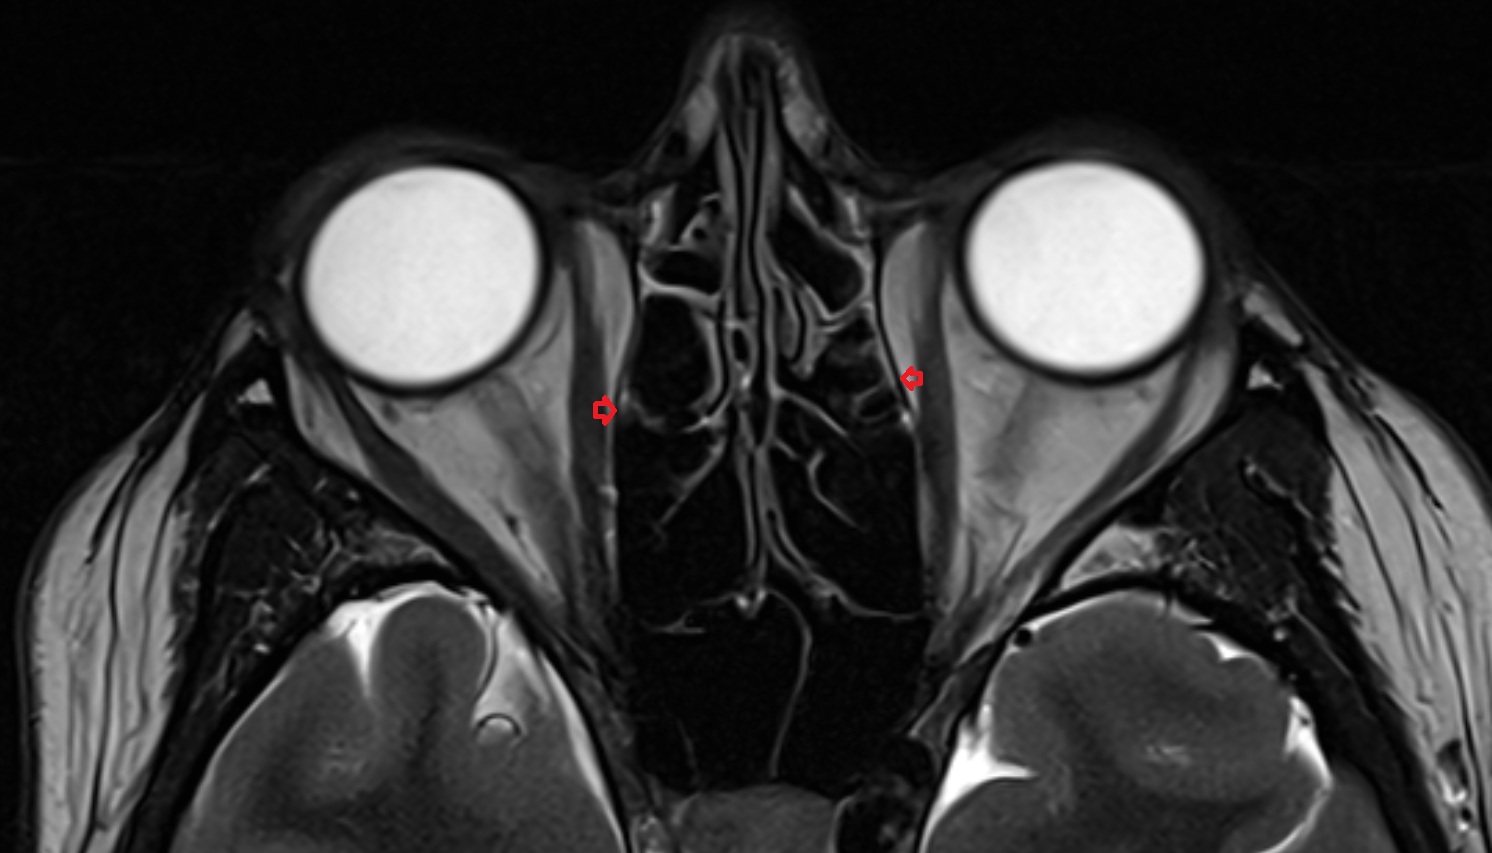

- Orbital part of optic nerve

- Optic nerve sheath

- Subarachnoid space of optic nerve